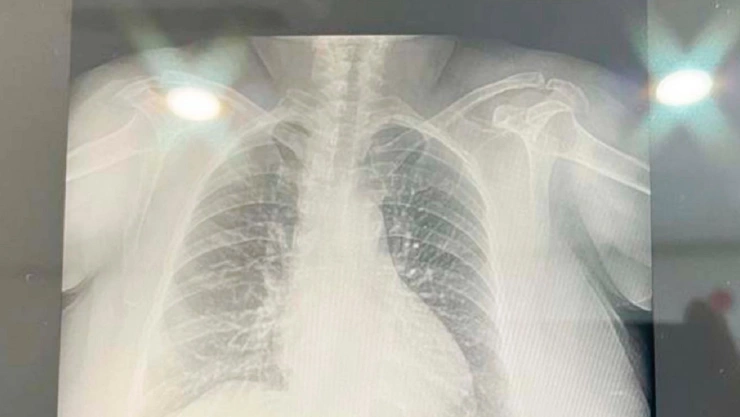

La reciente actividad del volcán Popocatépetl ha provocado que diversos municipios de la entidad se cubran de ceniza. Ante esto, diversas personas han presentado algunos malestares, entre los que destacan los síntomas respiratorios, debido a la prolongada exposición a la arenilla. Pero, ¿sabías que estas afecciones pulmonares se deben a la enfermedad denominada volcanoconiosis?

De acuerdo con la autoridad estatal de Puebla, la volcanoconiosis es un conjunto de afecciones respiratorias crónicas provocadas por la caída de ceniza.

Su nombre completo es Pneumonoultramicroscopicsilicovolcanoconiosis, y de acuerdo con Oxford English Dictionary, se refiere a la "enfermedad pulmonar producida por la intoxicación de sílice", es decir, respirar ceniza de un volcán.